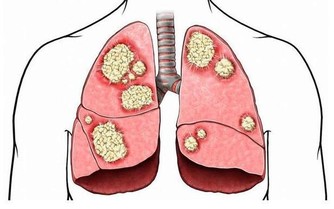

但是,持久劇烈的咳嗽不僅影響休息,還會消耗體力,甚至將病變擴散到鄰近的小支氣管,誘發肺炎、肺氣腫等重大疾病。所以,選止咳藥時,要先弄清病因。

潤喉生津、潤燥利咽、止咳化痰、健脾開胃、美白淡斑、減肥去脂。常用語暑熱,咽炎炎症,咳嗽痰多、小兒百日咳等,對喉嚨痛、咽喉炎、聲音嘶啞、肺燥乾咳效果好。